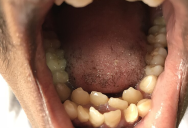

Normal adult humans have 32 teeth. Rarely, someone has a condition called hyperdontia where they have more than 32. This happens with around 1-2% of the population.

Sometimes, those with hyperdontia barely even notice the difference. This is common when someone has just one or two extra teeth. In fact, they may not even notice until their dentist tells them about their abnormality.

As long as it isn’t causing any issues, the person with extra teeth can live normally without taking any action at all.

Other times, hyperdontia can cause serious issues. This is most common when the person has a large number of extra teeth. Depending on where they come in, the extra teeth may cause jaw pain, over-crowding, difficulty with brushing or flossing, cosmetic issues, and more.